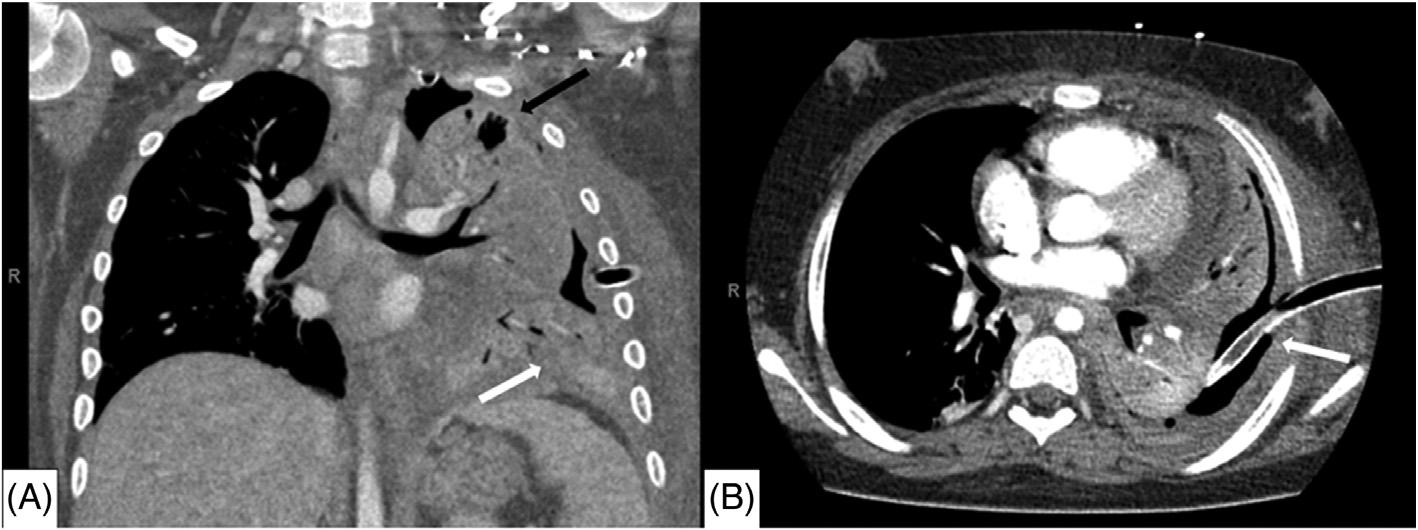

Initiallaboratoryresultsareshownin Table.An electrocardiogram(ECG)wasperformedandshowedasinus rhythmwithoutectopyorST-segmentchangesandwas unchangedfromhisprevioushospitalization.Chest radiography(CXR)wasobtained,shownin Image1.The radiologist’sinterpretationwas “[p]atchyopacityintheright lowerlobesuggestiveofpneumoniainthecorrectclinical setting.Goiterredemonstratedwhencomparedtoprevious. Normalcardiac findings.” Apoint-of-careultrasound (POCUS)oftheheartshowednopericardialeffusion,no suggestionofrightventriclestrain,novolumeoverload,and anormalleftventricle.

Image1. Initialchestradiographshowinganopacityintheright midlung(blackarrow)ina77-year-oldmanbeforeheexperienced arapidchangeinmentalstatus.

Thepatientwasintubated,andaconfirmatoryCXR demonstratedintervalchangesofanewleftIJcentralline catheterandanendotrachealtubethatbothappeared adequatelypositionedasseenin Image2.

Repeatchestradiographofa77-year-oldmanaftera rapidchangeinmentalstatusshowingtheplacementofan endotrachealtube(blackarrows)andleftinternaljugularcentral line(whitearrows).

ThepatientunderwentanemergentCTofthehead (Image3)duetothechangeinmentalstatus.Theradiology impressionoftheCTrevealed “extensivevenousgas,which

Computedtomographyofthebrainofa77-year-oldman afterarapidchangeinmentalstatusshowingextensivevenous gas(whitearrows)intherightparieto-occipitalregion.

mayindicategasemboluswithpossibleevolvinginfarctionin therightparietalregion.Nohemorrhageorshift.Further evaluationwithmagneticresonanceimaging[MRI]maybe useful.Largegoiter.” Immediatelytheteamassessedthe patient’scentralvenouscatheterandfoundanuncappedline. Aftertheairwaswithdrawnfromtheline,thelinewas capped.Thepatientwastransferredtotheintensivecareunit atourhospitalforfurthermanagementandahyperbaric medicineconsultation.Heunderwentahyperbaricoxygen therapytreatmentwithresolutionofthegasontherepeatCT head.Afollow-upMRIrevealedmultifocalinfarctsin multiplevascularterritories.